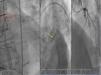

Three patients presented with new-onset crescendo angina reaching III/IV on the Canadian Cardiovascular Society (CCS) angina grading scale, and two had acute coronary syndrome (non-ST elevated myocardial infarction). The coronary angiogram showed CTO of the semi-protected LMCA lesions with two coronary artery bypass grafts previously performed in all patients, one occluded and the other patent (Figure 1). Three patients had saphenous vein grafts to the circumflex coronary artery that were CABG occluded and two patients had left internal mammary artery-left anterior descending artery CABG failure. A coronary CT angiography was performed in one patient to better visualize the CTO (Figure 1).

(A and B) Coronary angiogram showing chronic total occlusion of the left main coronary artery and critical left anterior descending lesion proximal to left internal mammary artery anastomosis; (C) coronary computed tomography angiography showing a short (9 mm), hardly calcified chronic total occlusion lesion: in the middle of the occlusion 100% of the coronary lumen (186 Hounsfield units) was calcified and, in the distal part, 75% of the wall circumference (933 Hounsfield units) was calcified.